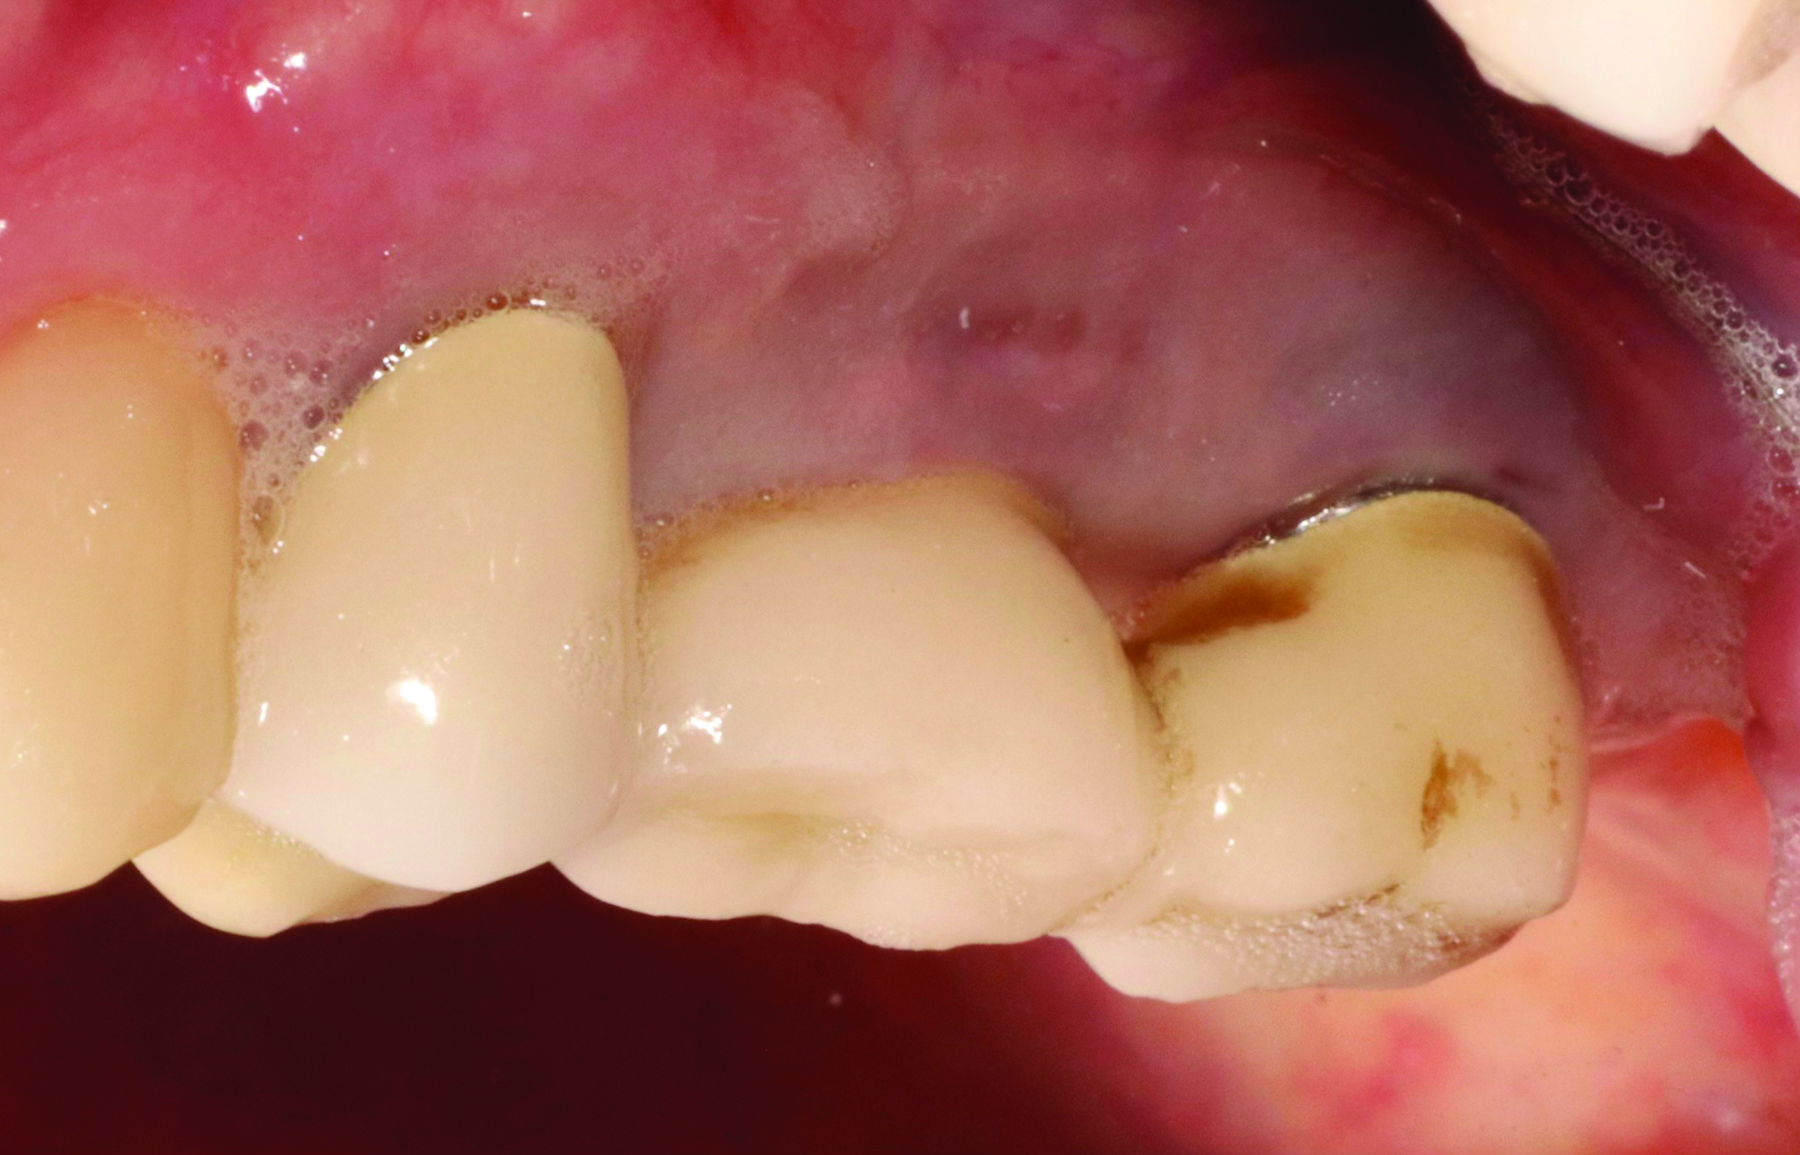

Fig 2. A patient presented with inflammation around implants. The patient was having difficulty brushing the area due to a shallow vestibule, the proximity of the implants, and a lack of keratinized tissue surrounding the implants.

Figure 2

Tissue thickness has been shown to affect the initial crestal bone loss around dental implants.33 Linkevicius et al demonstrated that thick phenotypes had less initial crestal bone loss than thin phenotypes.33 However, when thin tissues were augmented with human soft tissues (allografts), the crestal bone loss was comparable to thick tissues.33 Therefore, a thicker phenotype is more desirable when evaluating soft-tissue quality around dental implants, and this aspect should be evaluated during maintenance visits. Additionally, the amount of keratinized tissue may affect the long-term prognosis of dental implants. In natural dentition, at least 2 mm of keratinized tissue reportedly is necessary to maintain health of the periodontal tissues.34,35 For dental implants, however, the significance of keratinized tissue in preserving implant health has been less clear, with some early studies showing no association between the amount of keratinized tissue and bone loss and some studies reporting that the presence of keratinized tissue significantly decreases the amount of recession and clinical attachment loss.34-36 Additional studies support a band of keratinized tissue of more than 2 mm to be associated with decreased BOP, plaque, mucosal recession, and attachment loss,34,37 especially when patients are not on a strict maintenance protocol.38 This may be because keratinized tissue provides increased comfort for the patient during home care regimens, whereas pain with brushing and therefore a reluctance to upkeep maintenance may occur with thin peri-implant mucosa (Figure 2).39 As a result, during supportive peri-implant therapy, adequate evaluation of soft-tissue quality around dental implants is crucial, with recommendations for soft-tissue augmentation if needed (Figure 3 and Figure 4).